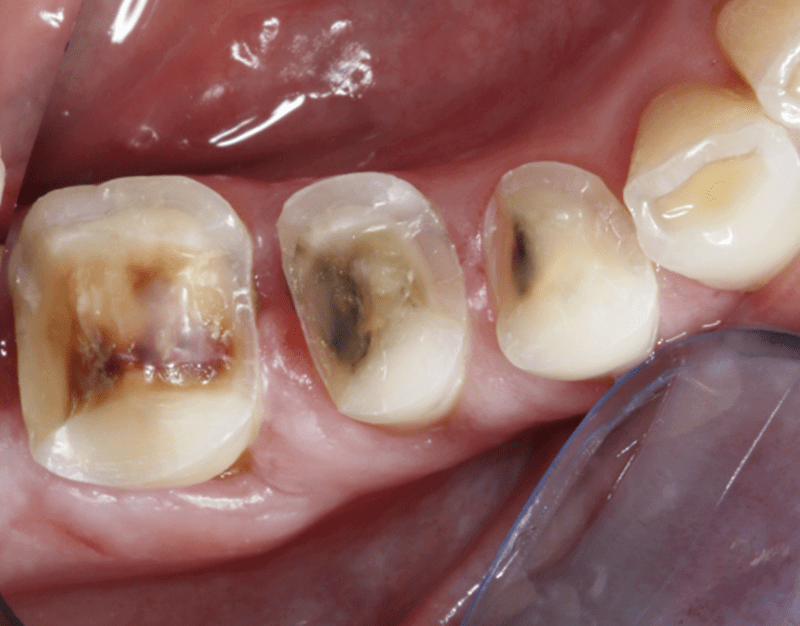

A kiindulási állapoton látszik, hogy a régi amalgámtömések szélei elváltak a fogtól, vagyis nem nyújtanak kellő védelmet. Az amalgámtöméseket a higanytartalmuk miatt amúgy is lassan megszüntetik, úgyhogy minden amellett szólt, hogy kicseréljük őket.

Amalgámtömések cseréje betétekre előtte